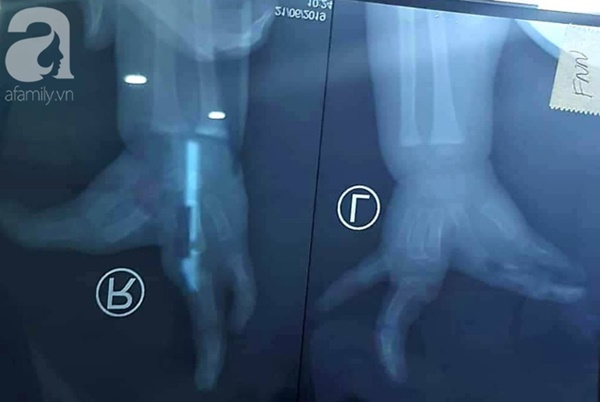

Ảnh chụp X-quang cho thấy các dị tật ở hai bên tay.

Bé được đánh giá phân loại dị tật loại 3, dính ngón 1 và 2 phức tạp, không có kẽ ngón. Thương cho hoàn cảnh gia đình và không thể chần chờ hơn, các bác sĩ quyết định tái sinh cho tứ chi dị dạng của em sau kiểm tra sức khỏe tổng quát ổn định.